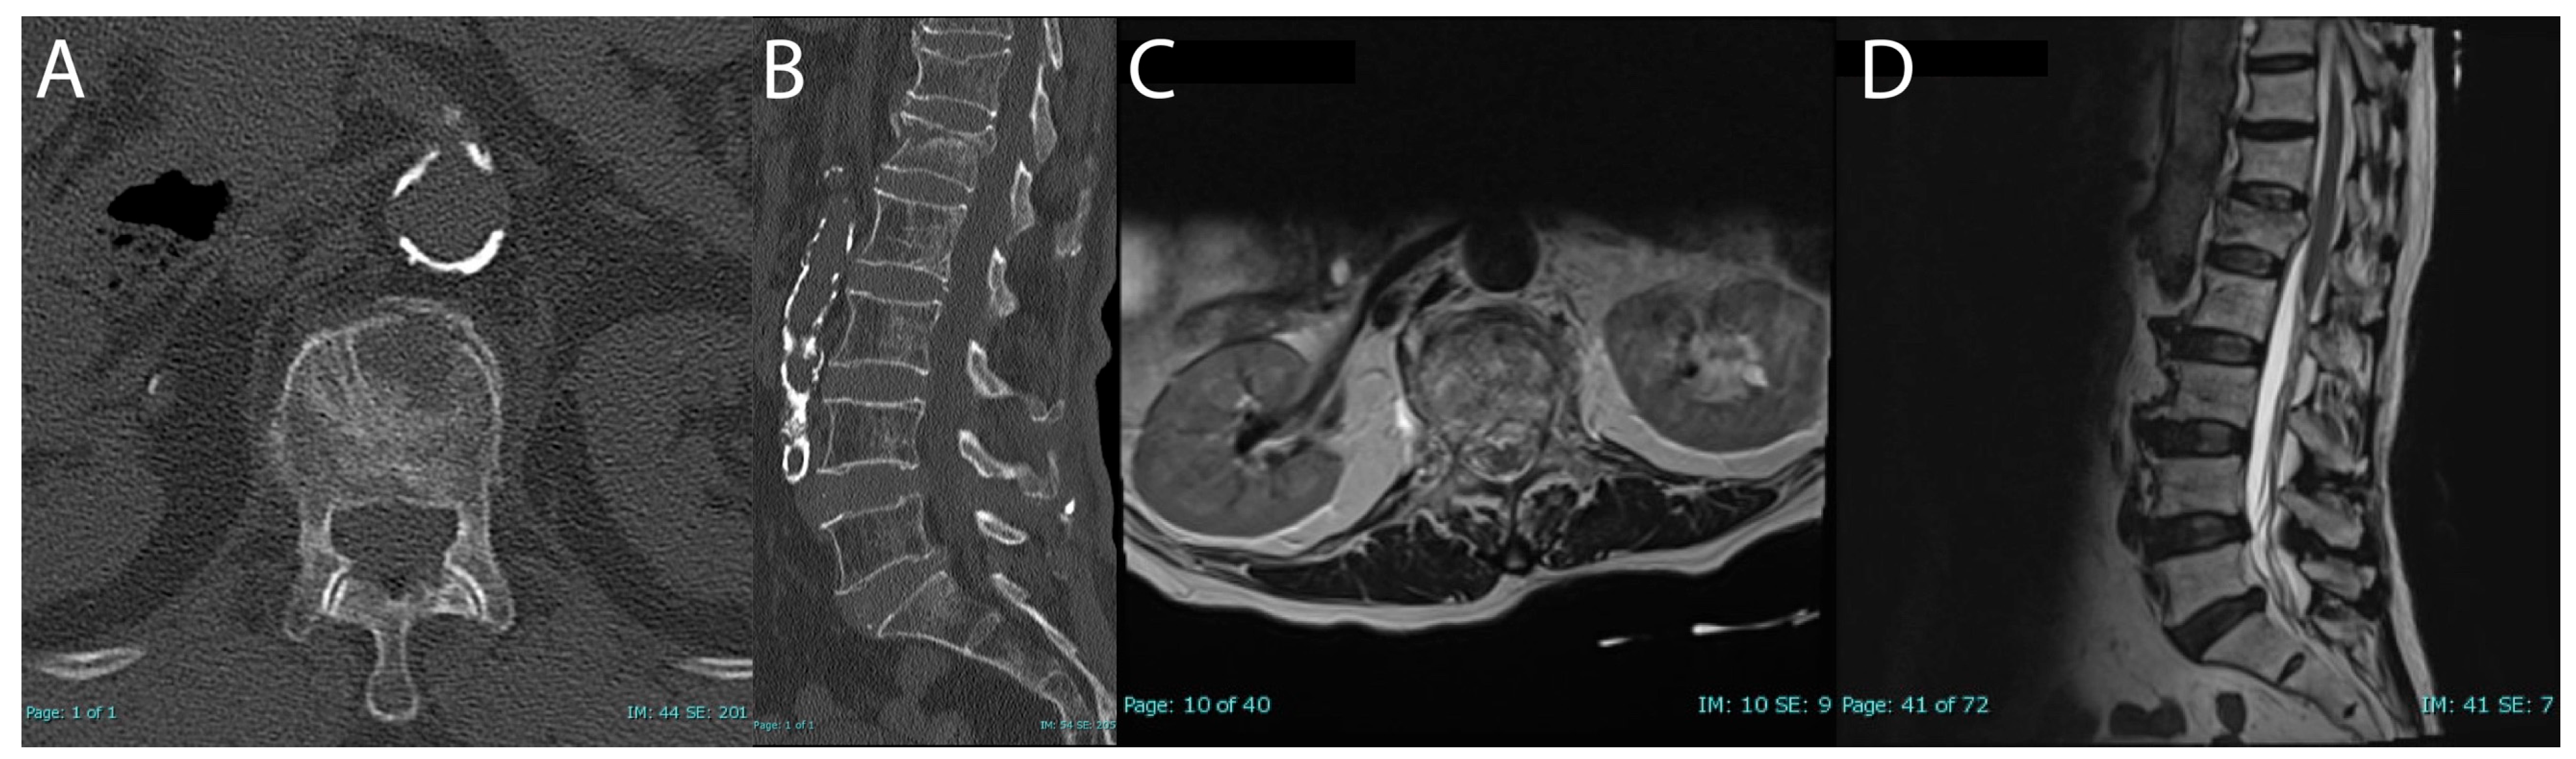

CT and MRI confirmed an acute two-column L1 vertebral compression fracture with approximately 26% height loss and 4.3 mm of retropulsion (Figure 2). Additionally, there was evidence of a mild chronic T12 compression fracture. MRI did not reveal ligamentous injury.

Figure 2. Preoperative CT and MRI assessment of burst fracture (AD); admission CT axial (A); CT sagittal (B); admission MRI axial T2 (C); MRI sagittal T2 (D).